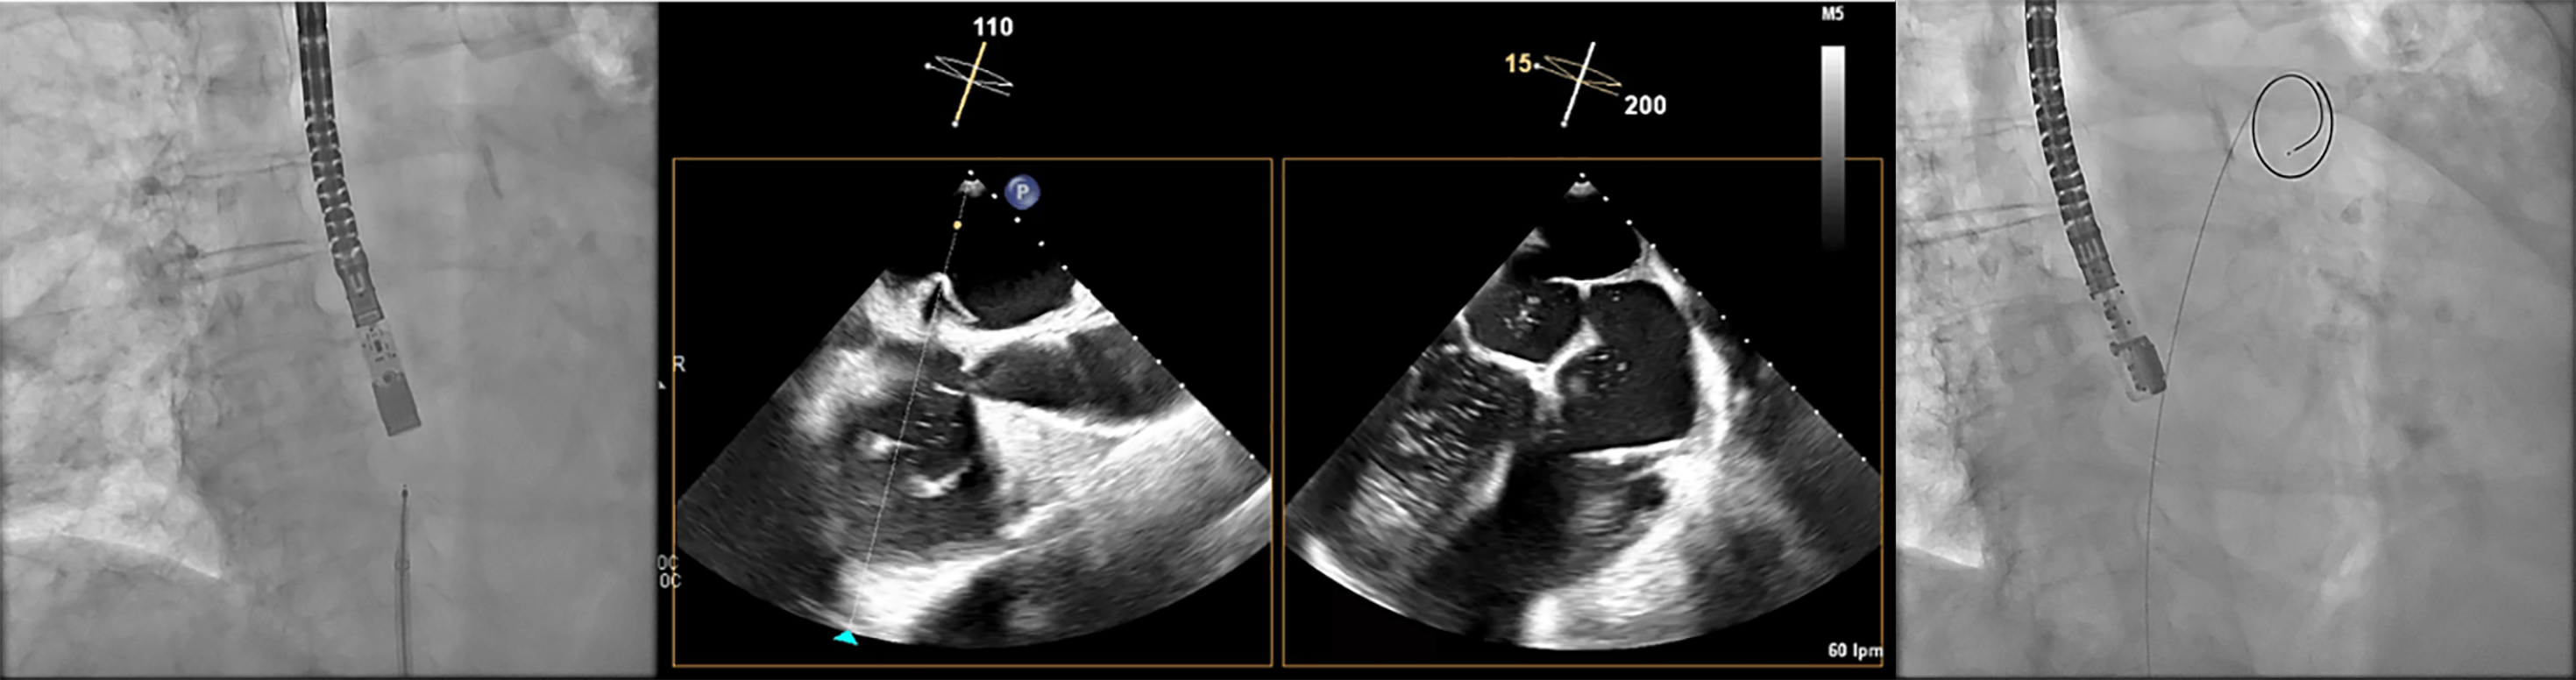

Immediately after a successful TSP, additional unfractionated heparin is given to reach a total dose of 100 U/kg. Then, the pigtail-shaped guidewire, which offers high support, is advanced and coiled within the LSPV by gentle clockwise rotation. This position allows smooth advancement of the VersaCross sheath into the LA for septal dilation. We maintain the same wire in the LSPV for the subsequent advancement of the dedicated LAAC delivery sheath (Fig. 8). Once the dedicated sheath reaches the LA and is positioned near the LSPV, a pigtail catheter is advanced over the VersaCross wire into the LA, after which the wire is withdrawn. With a gentle counterclockwise rotation of the assembly, the pigtail is directed and positioned within the LAA. At this stage, LAA angiography is performed in two standard projections: right anterior oblique (RAO) 30°/cranial 20° and RAO 30°/caudal 20°, which correspond to the 45° and 135° TEE views, respectively (Table 3). Guided primarily by TEE—and secondarily by angiography—the device size is selected following precise evaluation of the landing zone and theoretical device positioning within the LAA. Although several occlusion devices are currently available (Table 4), we provide a detailed procedural overview of two of the most widely used LAAC systems worldwide.

Fig. 8.

Advancement of the sheath over the VersaCross wire. The Versacross wire is positioned in the left superior pulmonary vein (LSPV), as seen in the fluoroscopy image (upper left) and confirmed by transesophageal echocardiography (TEE) (upper right). The dedicated sheath for left atrial appendage closure (LAAC) device was advanced successfully over the same wire up to the LSPV, as visualized by TEE (bottom image).